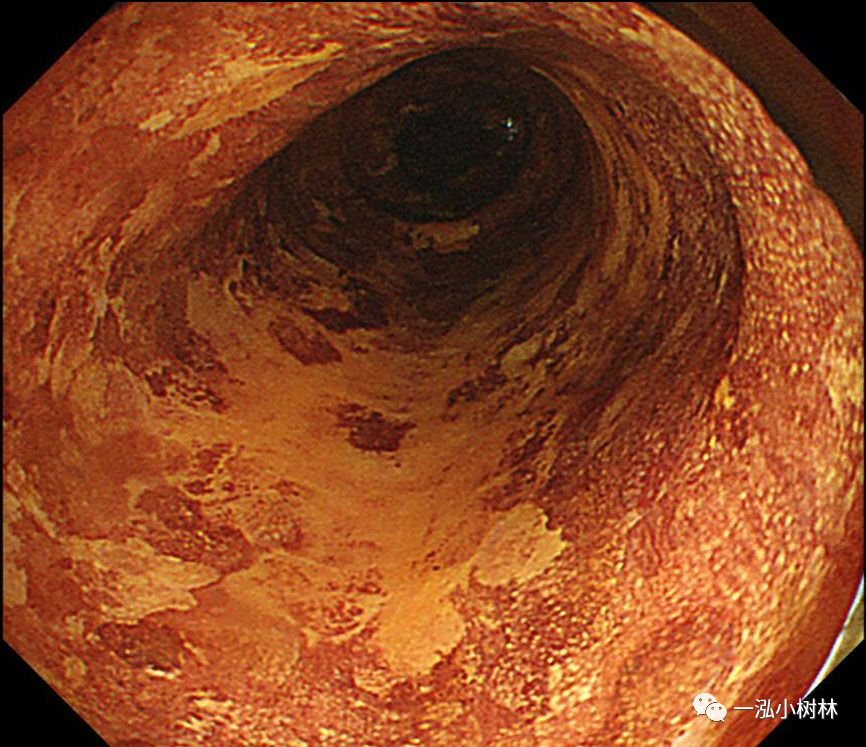

图3 碘染色:病变呈不规则拒染区